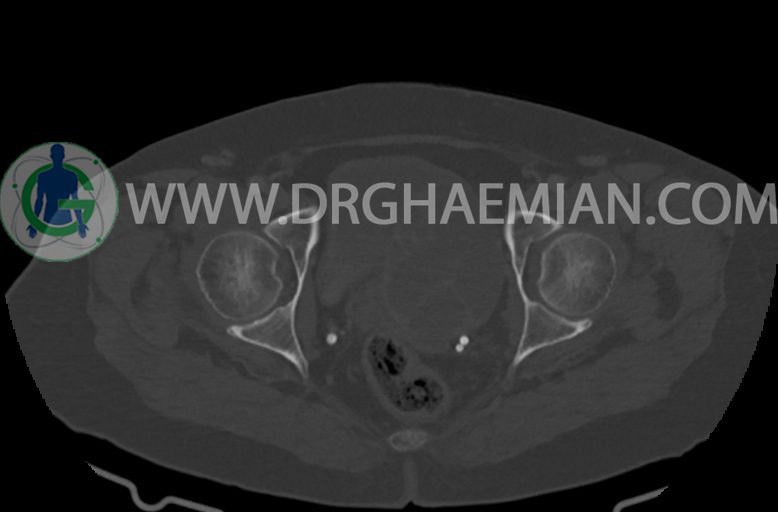

–ساختار Cystic multiseptate همراه با Enhancing thick septation به ابعاد 79x62mm در

لگن دیده می شود که در درجه اول مطرح کننده ی ضایعات نئوپلاستیک تخمدانی نظیر mucinous cyst adenocarcinoma است.

–شواهد هیسترکتومی

–ضایعه ی mass like هیپردنس- هتروژن به قطر 42mm در سمت راست لگن